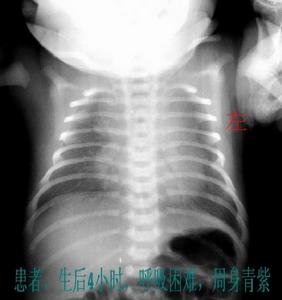

早產兒出生時心跳、呼吸亦可完全正常。一般出生後立即開始或在6小時內逐漸出現呼吸困難、青紫,伴呼氣性呻吟、吸氣性三凹征,並進行性加重。胸腹呼吸動作不協調,呼吸由快轉慢、不規則或呼吸暫停,青紫明顯。經急救後呼吸可好轉,但過後又復發,常呈原發性發作,程度漸次加重,持續時間延長,發作間隔縮短。體溫不穩定,往往不升。死亡多發生在出生後48小時內。部分病例經治療病情漸漸緩解,病程如能超過72小時,肺成熟度增加,則多數患兒能逐漸康復。

5、肺部X線檢查:按病情輕重可分四級。

第一級為細粟粒狀毛玻璃樣陰影,兩肺透亮度減低;

第二級除粟粒陰影外可見超出心影的空支氣管影;

第三級除上述影像外,心緣與隔緣模糊;

第四級為廣泛的白色陰影稱"白色肺",其中有黑色的禿葉樹枝狀空支氣管樹影由肺門向外周放射伸展至末梢氣道,形成"支氣管充氣征"。用高壓氧通入肺內,X線變化可獲改善。

3、輔助檢查:羊水泡沫試驗、胃液振盪試驗均呈陰性;羊水卵磷脂和鞘磷脂(L/S)<2∶1;血pH值、PaO2、HCO3-降低而PCO2、BE增高,呈代謝性酸中毒。血鉀早期常增高,恢復期利尿後可降低。肺部X線檢查早期兩肺有細小顆粒陰影,最後兩肺均不透明變白,伴有黑色“支氣管充氣征”。X線檢查應在用正壓呼吸前進行,否則萎陷不久的肺泡可以重新張開使胸片無陽性表現。